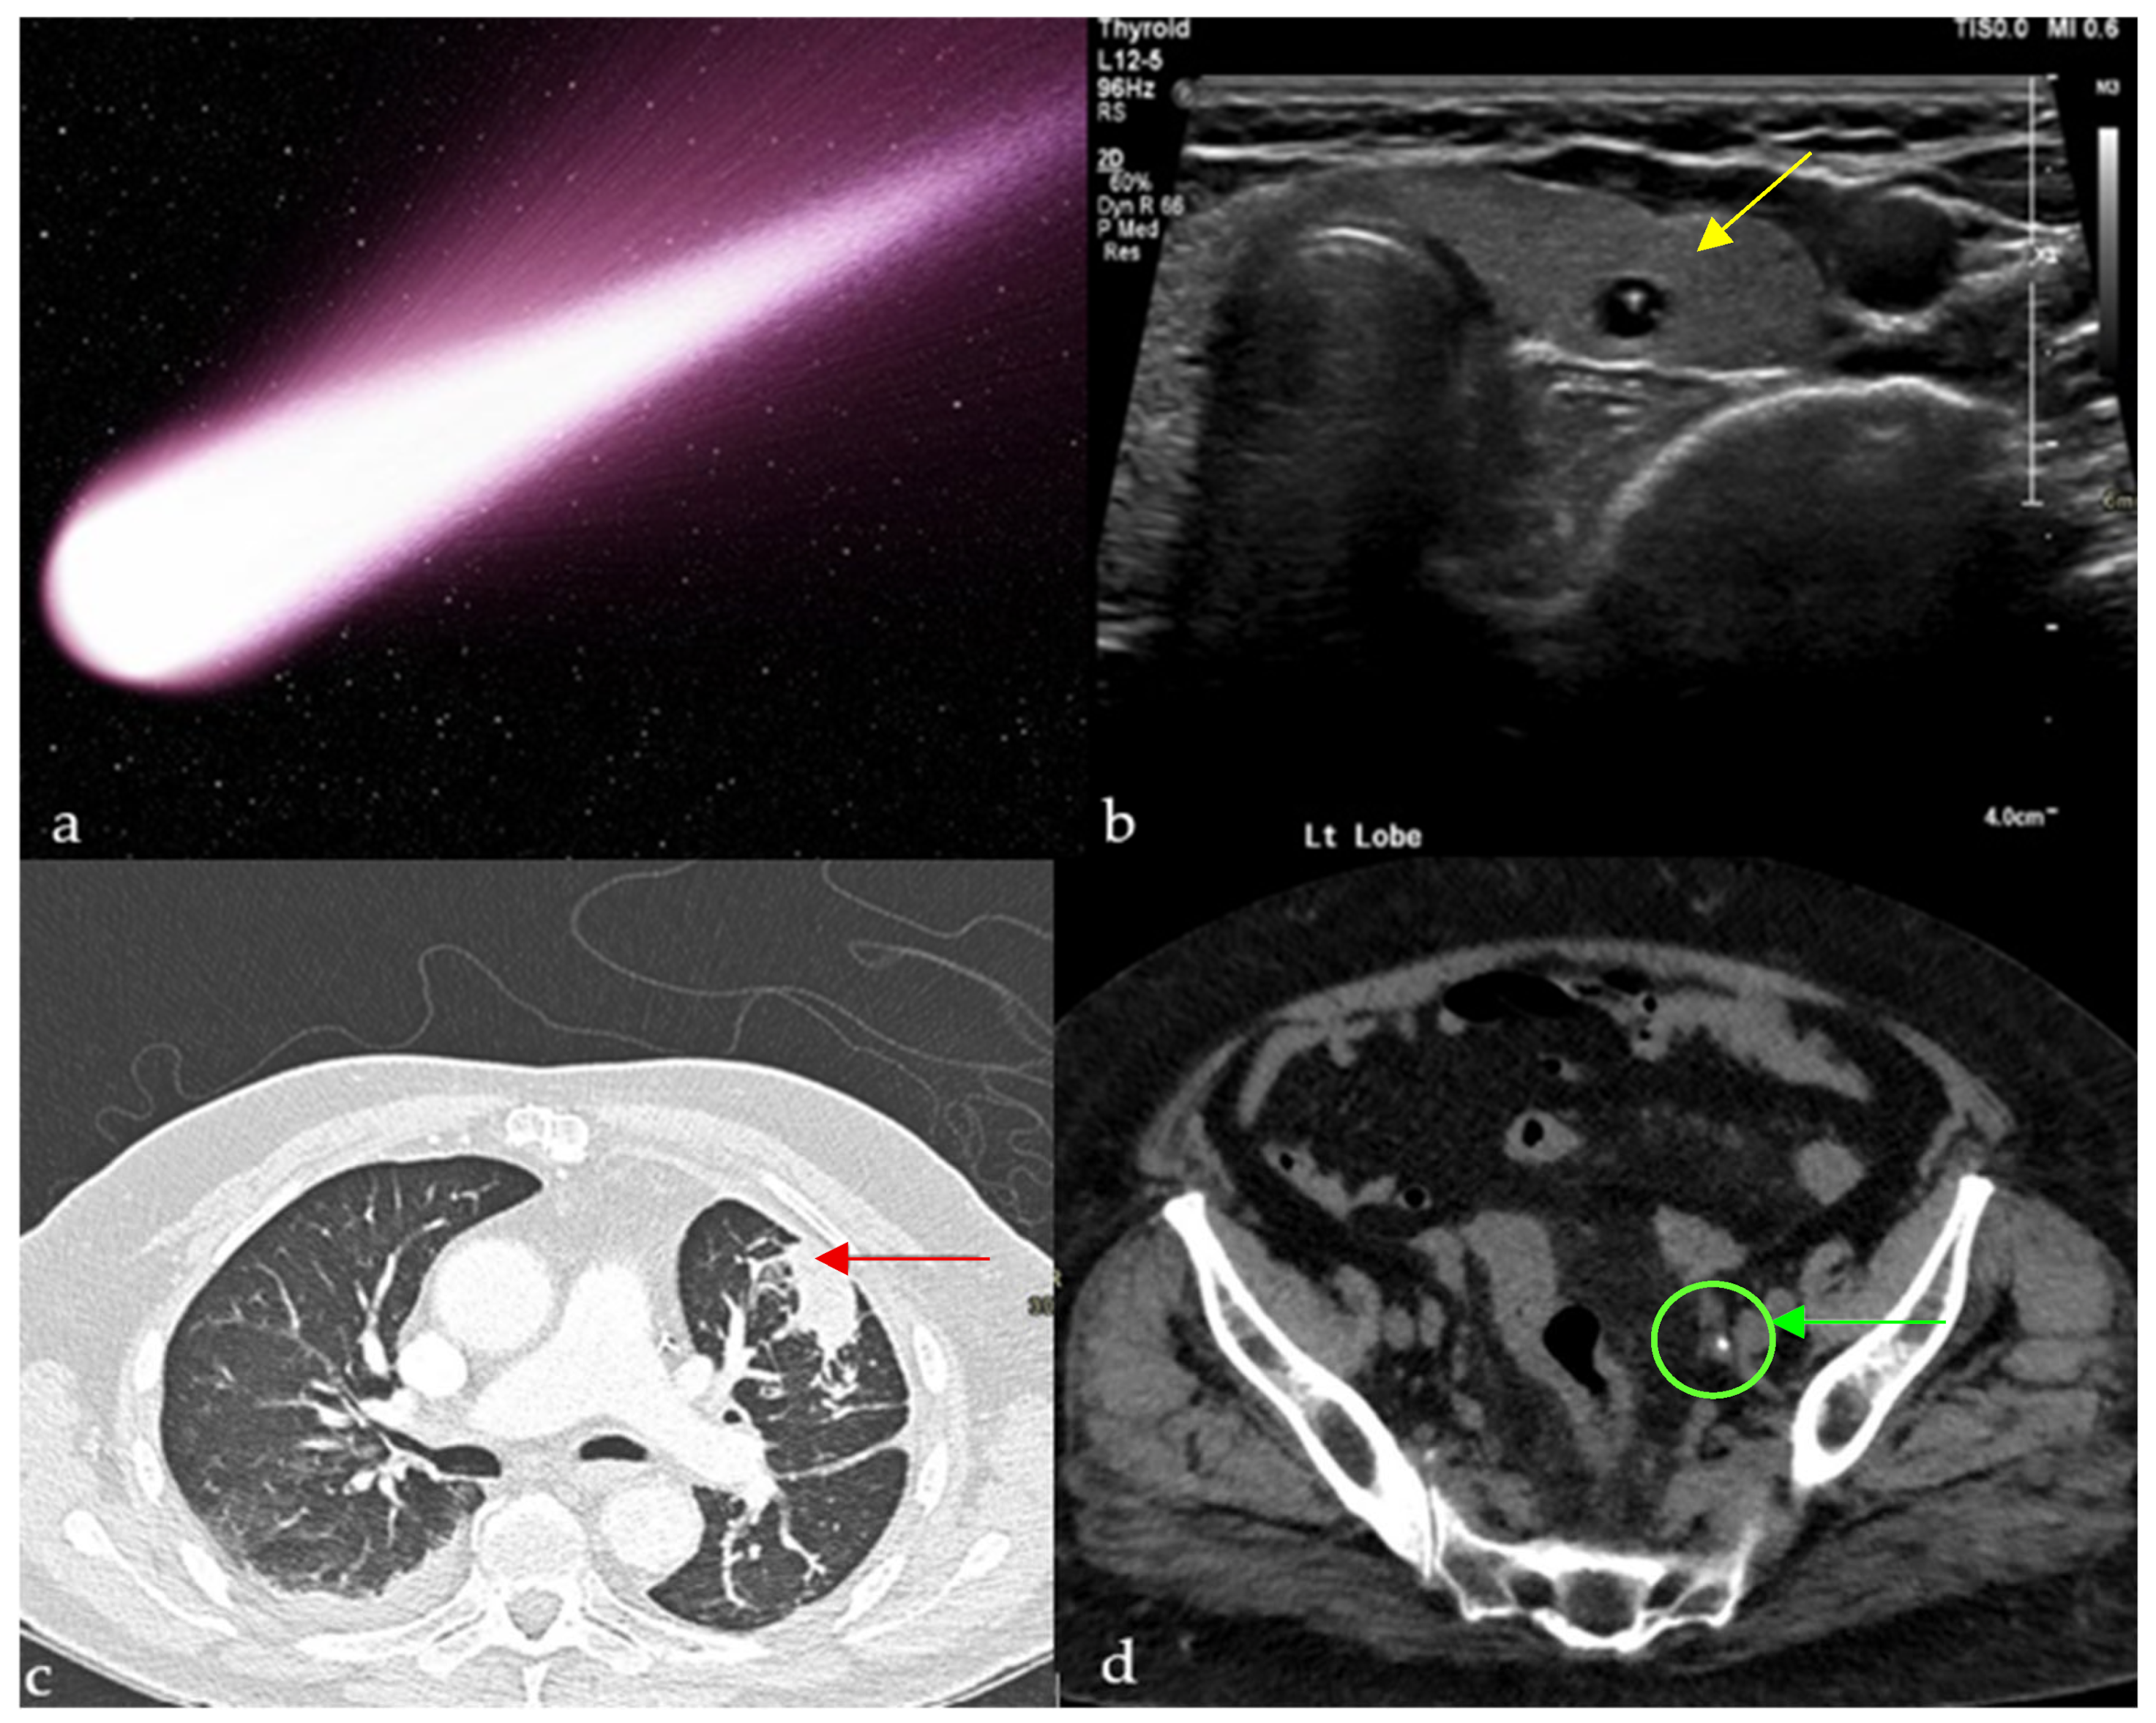

2.1. Comet-Tail Artifact

2.1.1. On Ultrasound (US)

2.1.2. On Computed Tomography (CT)

Chest

Abdomen and Pelvis